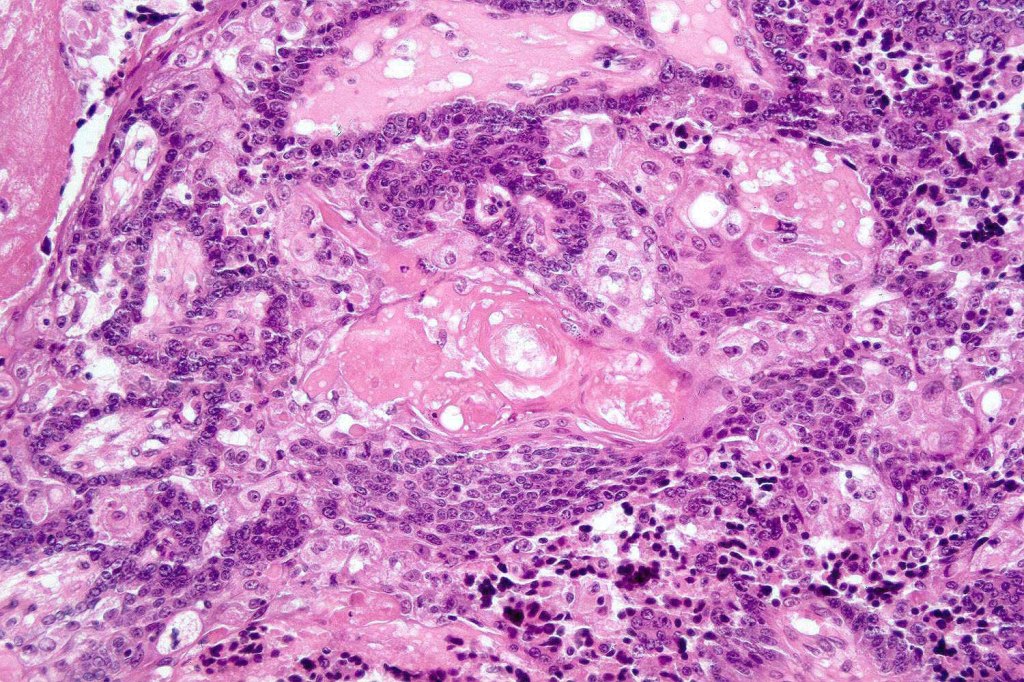

•Well differentiated lobular growth pattern though to a poorly differentiated tumor often showing a diffuse, infiltrating border which may extend into the subcutaneous fat

•Comedo type necrosis commonly present

•Tumors are composed of an admixture of darkly staining basaloid cells with hyperchromatic or vesicular nuclei and more obvious sebaceous cells with eosinophilic, bubbly, multivacuolated cytoplasm frequently indenting the nucleus (scalloped)

•Often mitoses are numerous and abnormal forms evident

Sebaceous carcinoma from a patient with Muir-Torre syndrome kindly shared by Dr. Antonina Kalmykova.